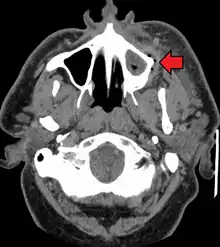

إذا تركت بدون علاج قد يصبح الخراج كبيرًا بشكل كافٍ ليثقب العظم ويمتد إلى الأنسجة الليفية فيتحة ل إلى التهاب العظم والنقي (osteomyelitis) والتهاب الهلل (cellulitis).من هناك يتبع الطريق الأقل مقاومة وينتشر إما داخليًا أو خارجيًا. مسار العدوى يتأثر بعوامل عديدة مثل موقع السن المصاب وسمك العظم، العضلات وروابط اللفائف.